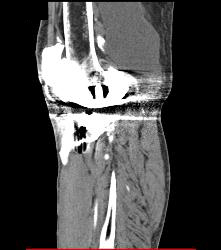

Diagnosis

Bakers Cyst